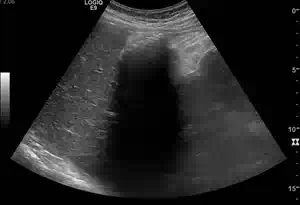

Pathologien der Gallenblase

Längsschnitt über der Gallenblase

Man erkennt an Stelle der Gallenblase lediglich ein breites, unregelmäßg begrenztes hartes Eintrittsecho mit dorsaler Schallauslöschung. Dabei handelt es sich um eine Schottergallenblase